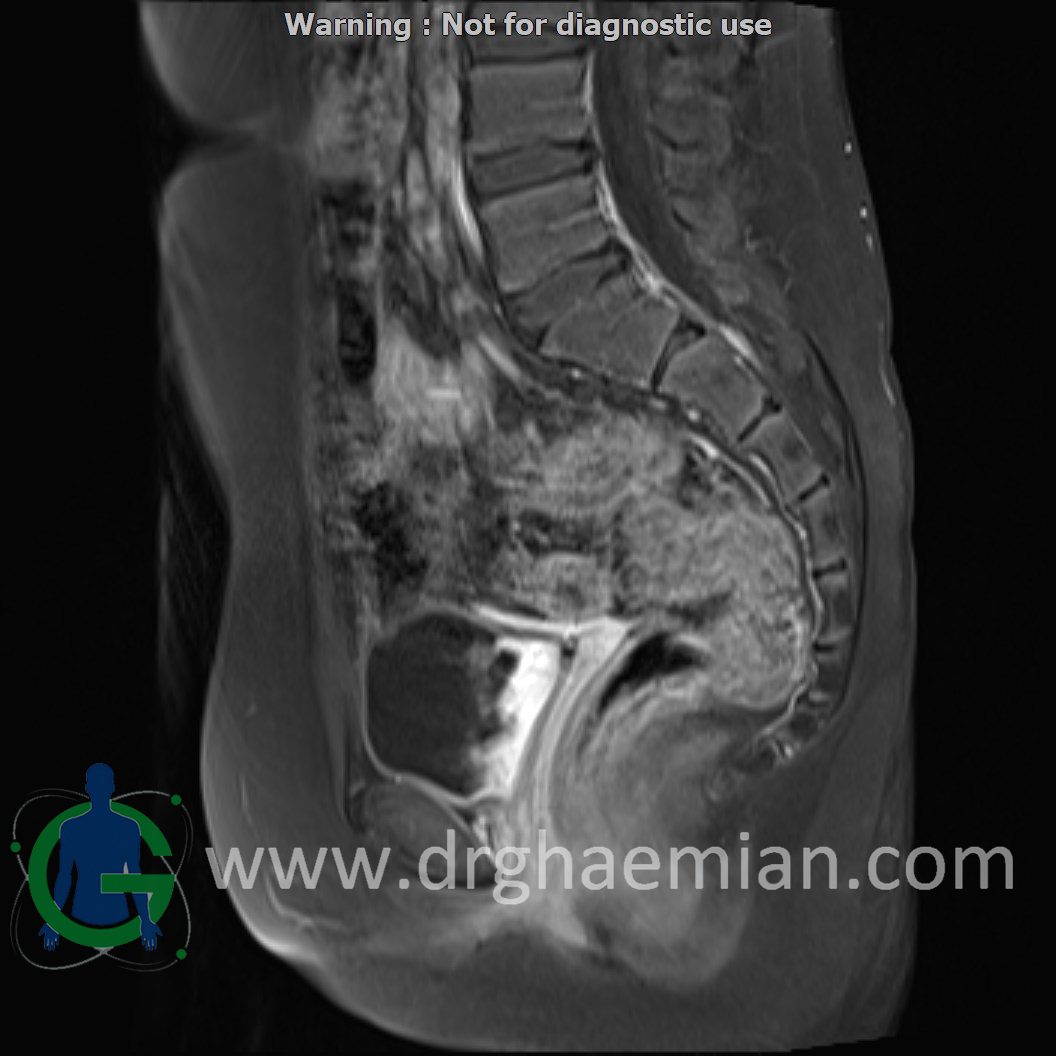

ام آر آی لگن یک روش تصویربرداری است که از طریق دستگاهی با آهنرباهای قوی و امواج رادیویی از ناحیه بین استخوان های ران تصاویری می سازد.در این کیس دیسژنزی غدد جنسی همراه با رحم و واژن هیپوپلاستیک نشان دهننده سندرم سویر ….

The uterus has normal internal structure and junctional zone is felt to be within normal limiths.

The adnexa appear normal on both sides.

Complete gonadal dysgenesis with hypoplastic uterus & vagina suggestive of swyer syndrome is seen.

Clinical crrelation is recommended.